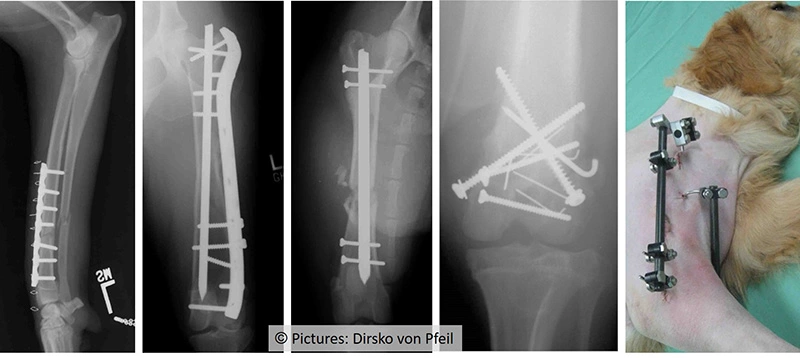

Frakturversorgung (Osteosynthese) klassisch

Knochenbrüche werden standardmässig mittels der am besten geeigneten Implantate versorgt.

Klassische Frakturversorgung mittels verschiedener Implantate. Bei korrekter Anwendung durch einen zertifizierten Orthopäden kann eine gute Heilung erwartet werden. Bilder: Dr. Dirsko von Pfeil.